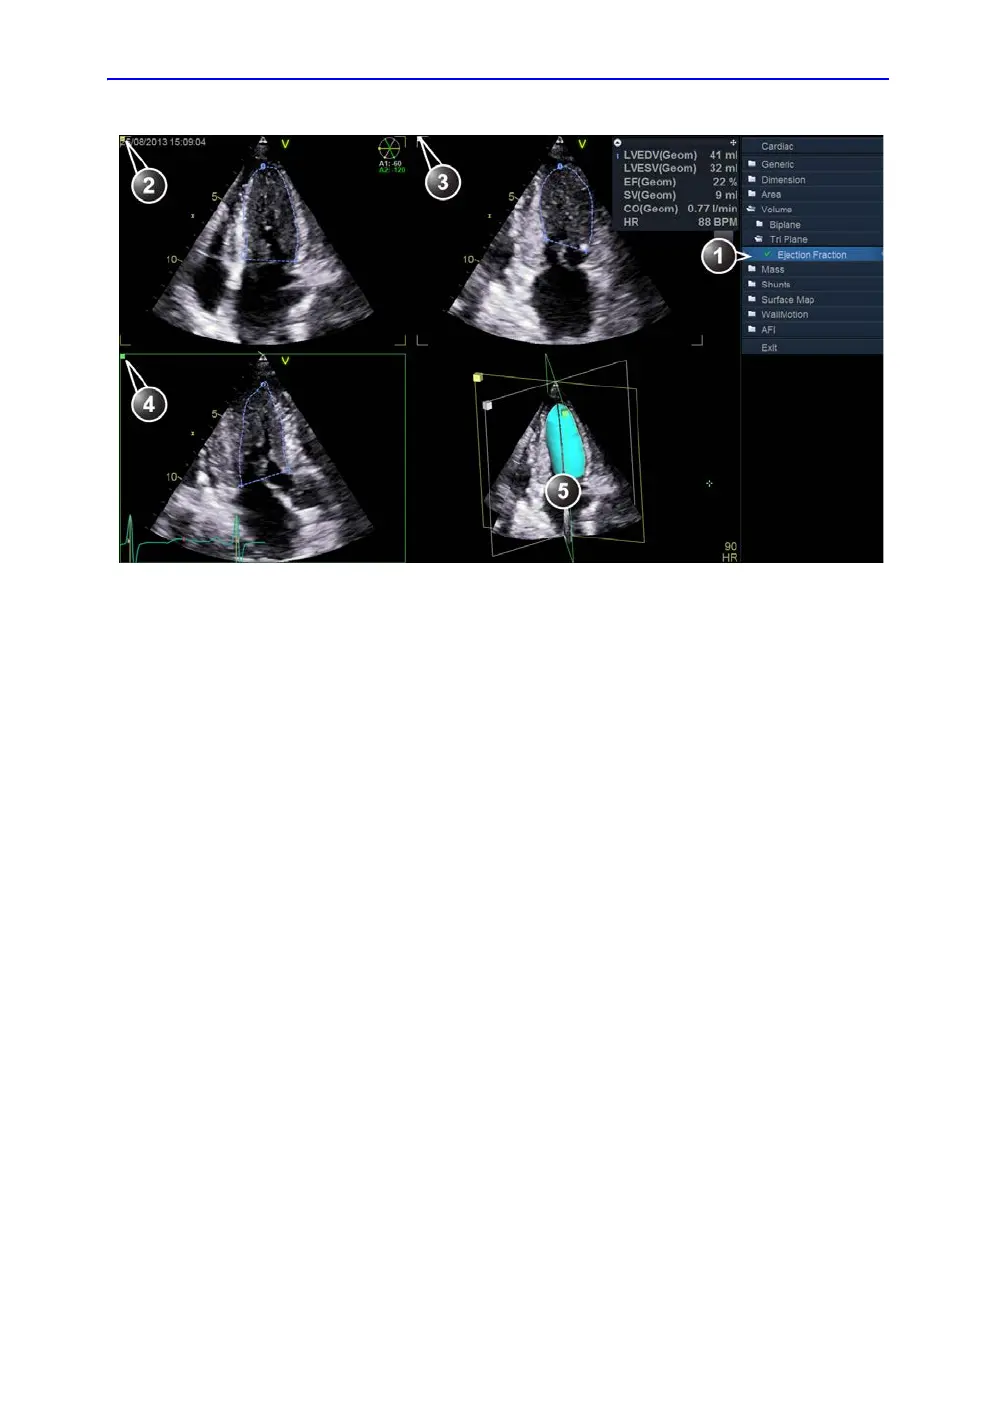

Figure 8-31. The Tri-plane measurement screen

1. Ejection fraction tool for Tri-plane

2. Scan plane 1 (yellow): Apical 4 chamber view

3. Scan plane 2 (white): Apical 2 chamber view

4. Scan plane 3 (green): Apical long axis view

5. Volume reconstruction